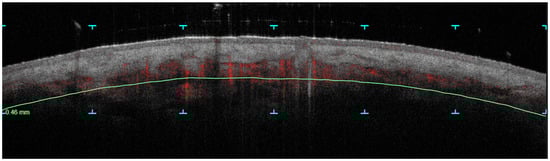

Figure 3.

Pixel density measurement on horizontal D-OCT 6 × 6 mm image. In this example of pixel density measurement on horizontal D-OCT 6 × 6 mm images, we used the ‘ImageJ’ software, a tool for image processing and analysis in Java, available for free in its 2014 version from the USA. This approach allows for the counting of pixels after reducing ‘background noise’ through a color saturation threshold set at 190 points. Pixel counting is performed by the software using the ‘measure analysis’ command, with outcomes displayed in a results box, which is highlighted here with a red square. Importantly, this image was acquired at a depth of 300 microns, allowing for the clear visualization of vascular structures.